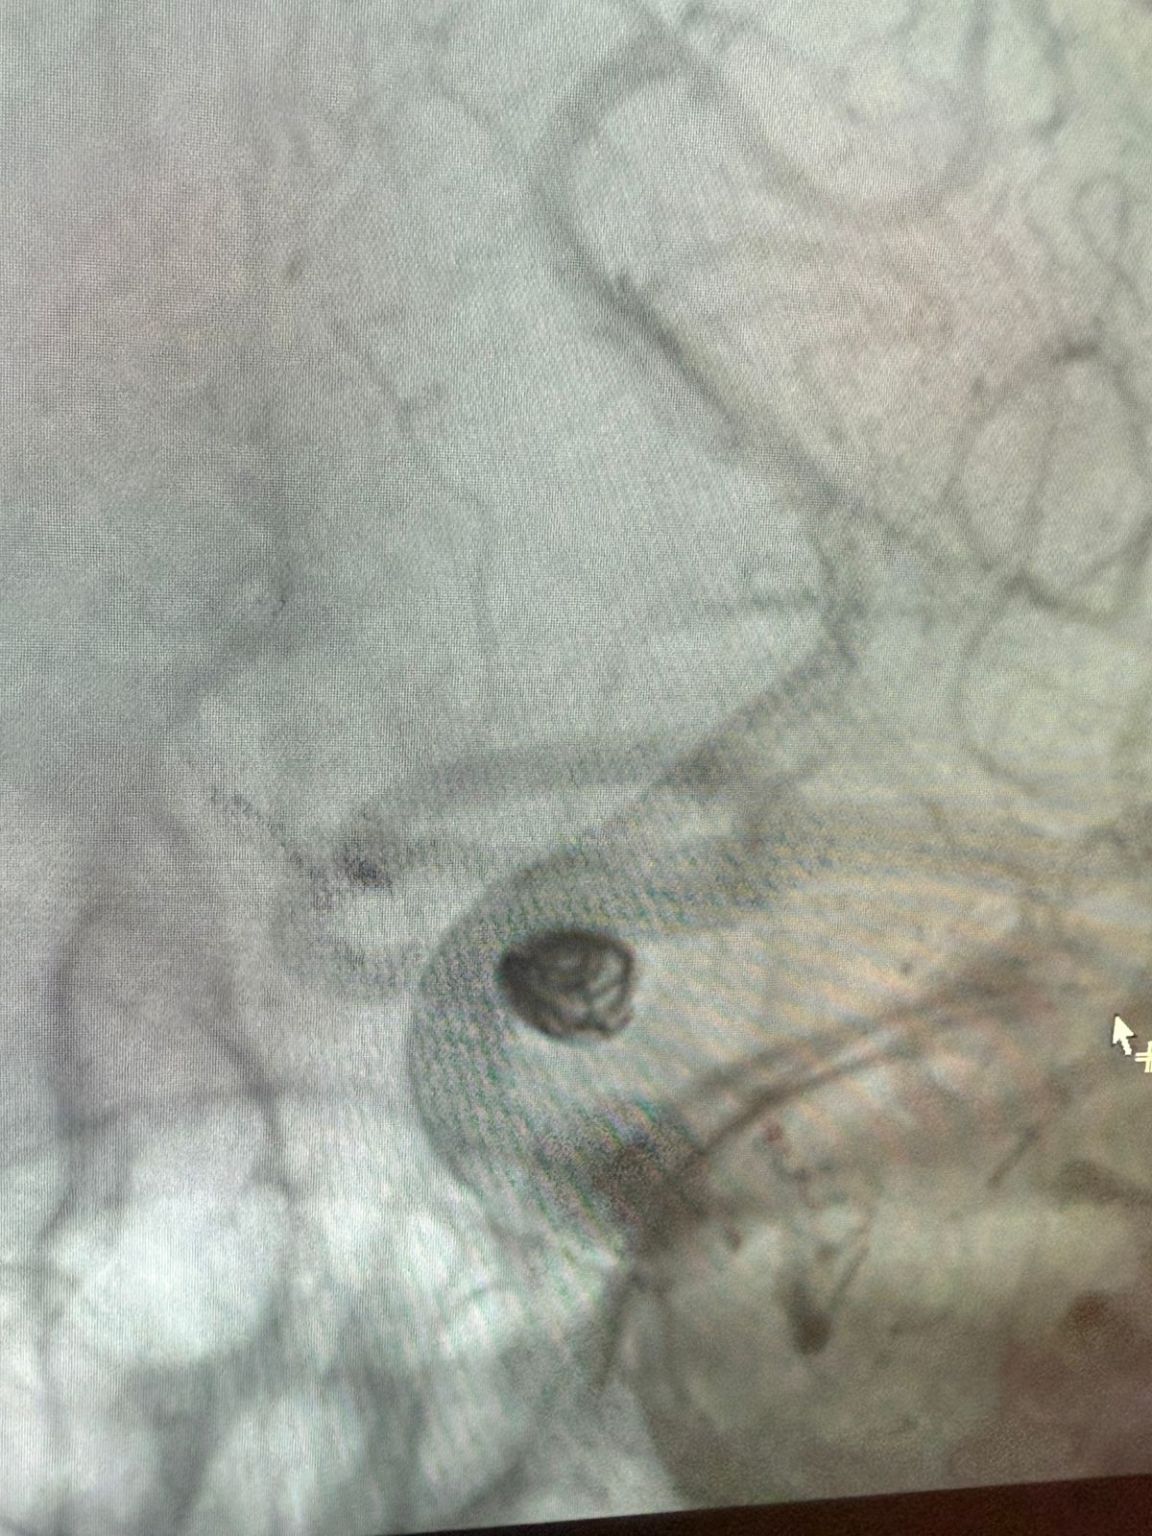

Мы рады поделиться недавней успешной процедурой в Клинике Альма Матер, Медельин, выполненной доктором Хорхе Мутисом.

Лечение использовалось Нува®Отвод потока (TJED-D 5,0-14), перденсатор®3D катушка и Frepass®Микрокатетер (TJMC18 Plus) для аневризмы задней сообщающихся артерий.

Доктор Мутис подчеркнул отличную видимость устройства и отметил, что извлечение было гладким. Он выразил большое удовлетворение в связи с окончательным результатом.